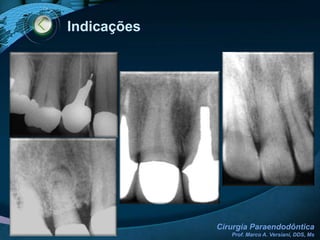

IndicaçõesGERAIS Estabelecimento de drenagem Alívio de dor Complicações anatômicas Problemas Iatrogênicos Traumatismos Falha em tratamento prévio Problemas durante o tratamento Necessidade de biópsiaESPECÍFICAS (ENDODONTIA)Impossibilidade de retratamentoExtravasamento de material obturador causando lesão periapical ou    sintomatologia dolorosaProcessos periapicais que não regridem após tratamento endodôntico (proservação)Fratura radicular com envolvimento pulparPerfurações radicularesReabsorções radiculares externasLesões periapicais de regressão duvidosa  e difícil acompanhamentoRetirada de corpos estranhos na região periapicalPersistência de exsudato nos canais radiculares

IndicaçõesGERAIS Estabelecimento dedrenagem Alívio de dor Complicações anatômicas Problemas Iatrogênicos Traumatismos Falha em tratamento prévio Problemas durante o tratamento Necessidade de biópsiaESPECÍFICAS (ENDODONTIA)Impossibilidade de retratamentoExtravasamento de material obturador causando lesão periapical ou sintomatologia dolorosaProcessos periapicais que não regridem após tratamento endodôntico (proservação)Fratura radicular com envolvimento pulparPerfurações radicularesReabsorções radiculares externasLesões periapicais de regressão duvidosa e difícil acompanhamentoRetirada de corpos estranhos na região periapicalPersistência de exsudato nos canais radiculares